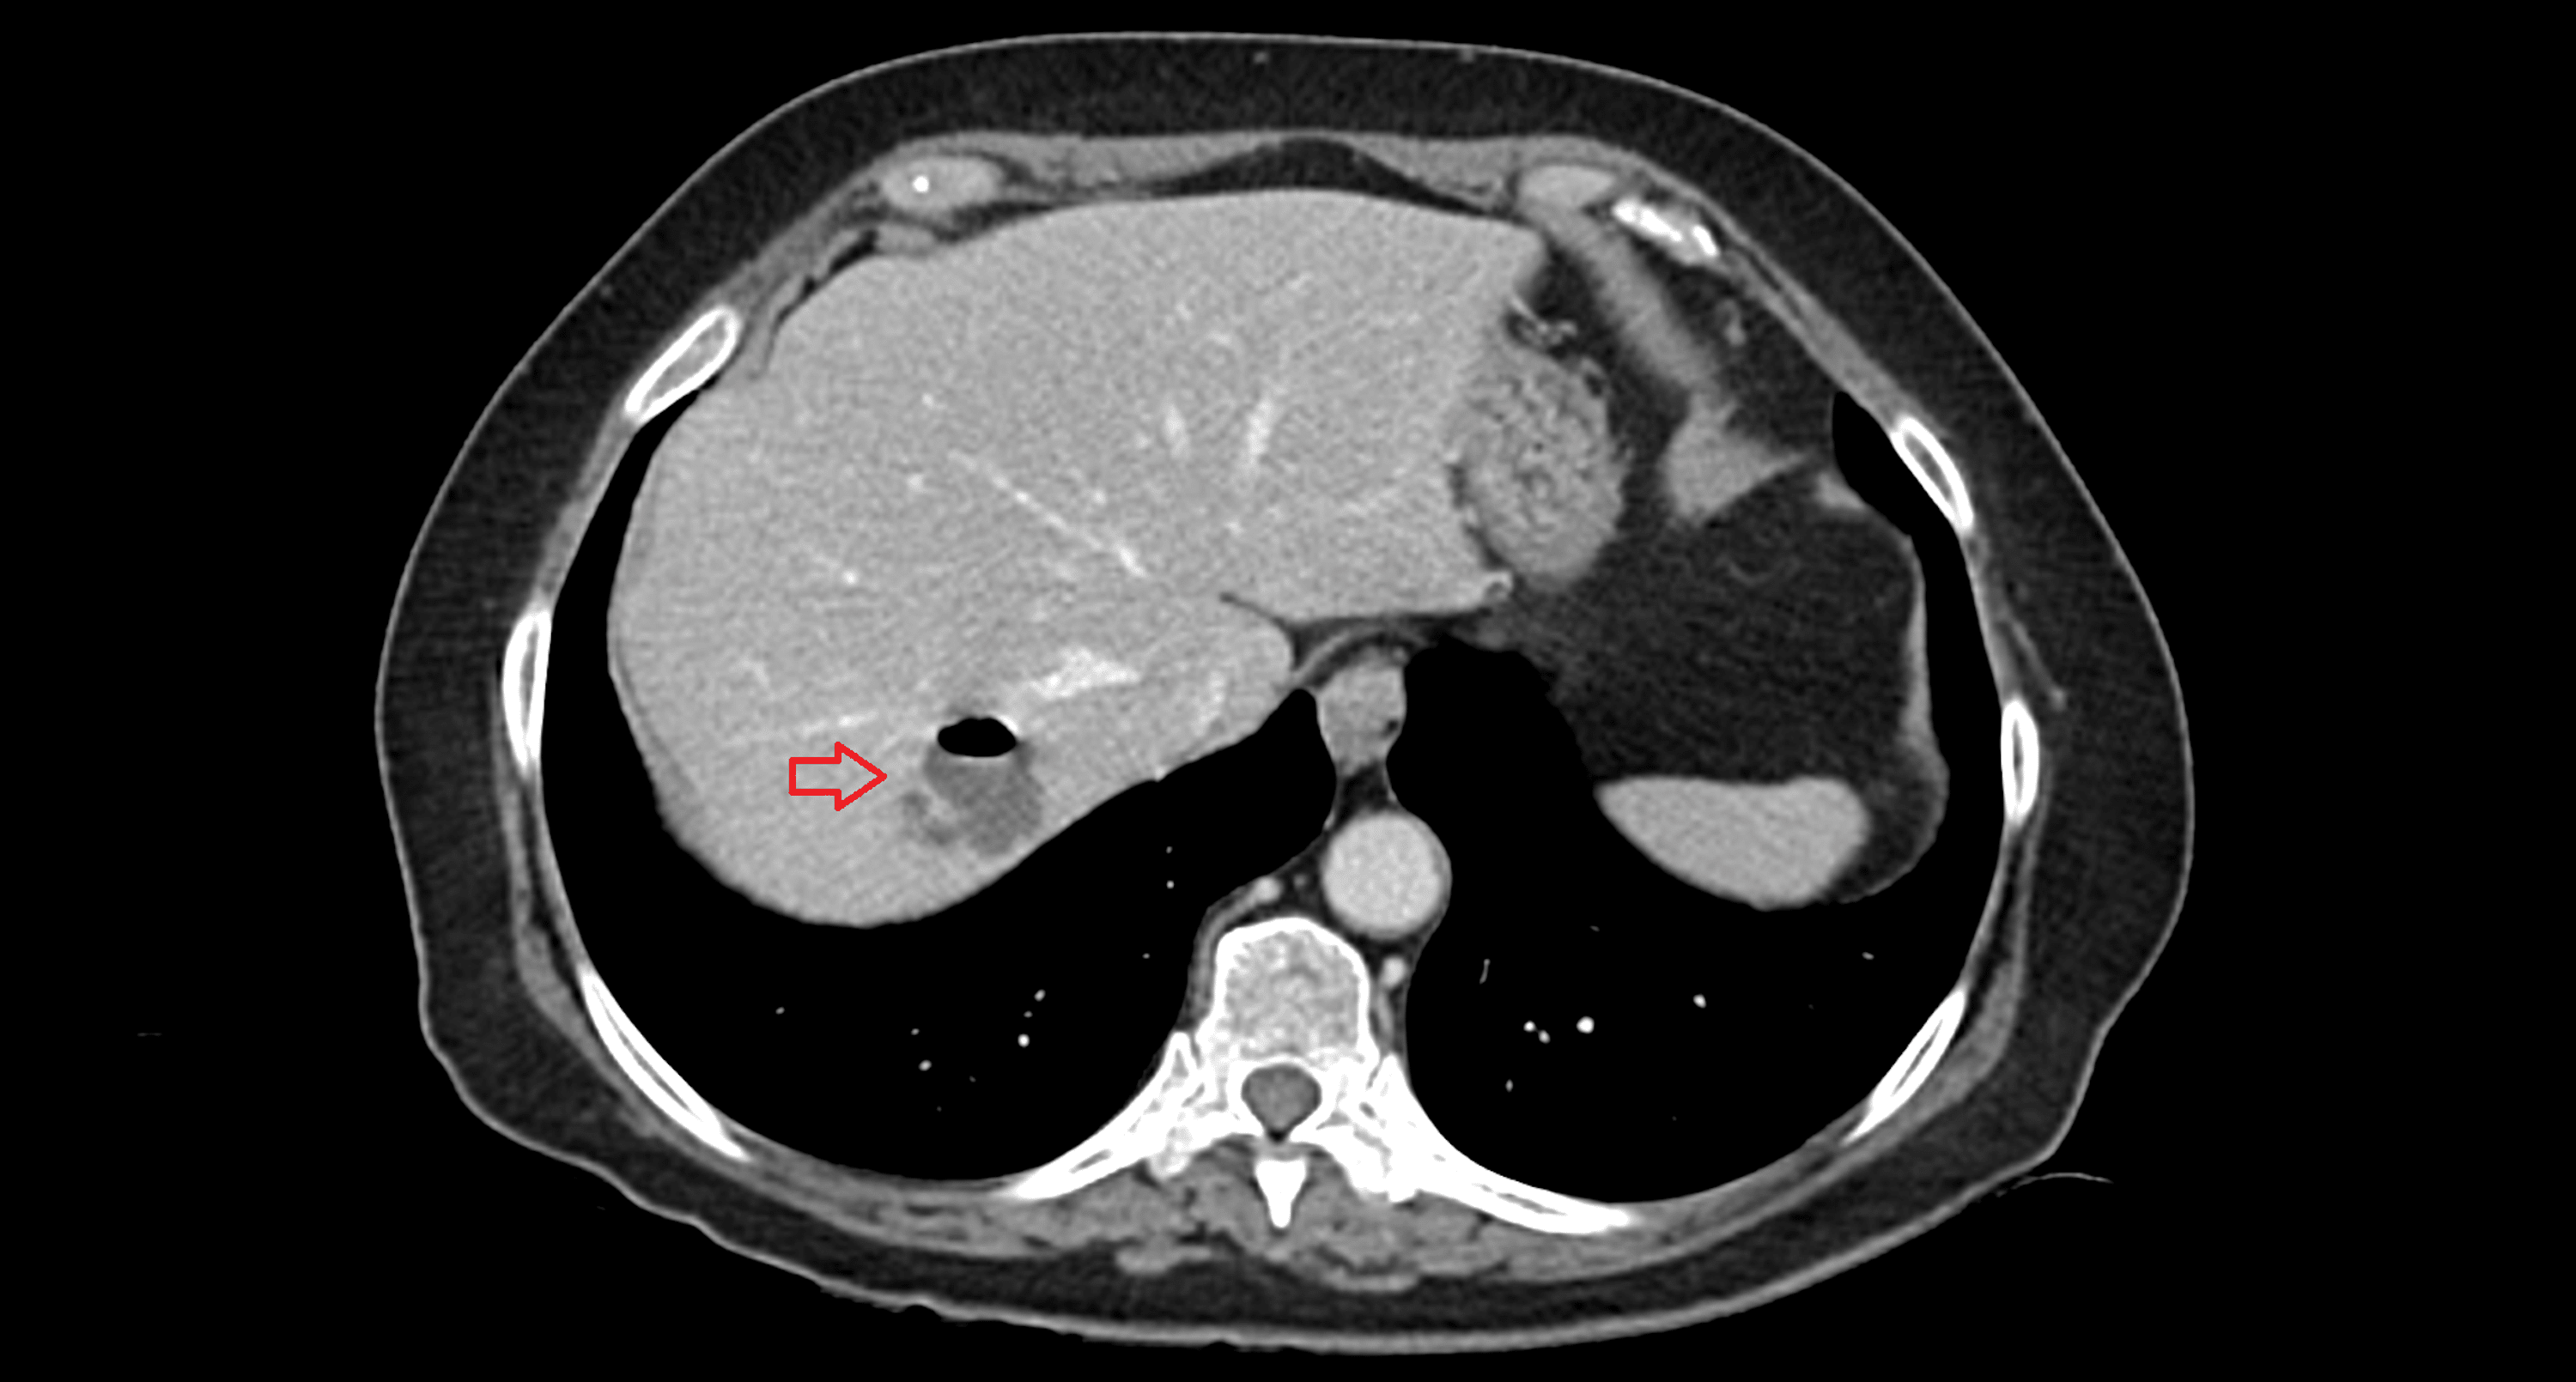

Pyogenic Liver Abscess Causes, Symptoms, Treatment and Cost Abscess Bleeding Abscesses are collections of pus in confined tissue spaces, usually caused by bacterial infection. — pus is a thick fluid that usually contains white blood cells, dead tissue and germs (bacteria). There are different types and they can appear anywhere on. The pus may be yellow. Smaller abscesses may not need. — a skin abscess is a tender. Abscess Bleeding.

Cureus Pyogenic Liver Abscess and Delayed Massive Gastrointestinal Abscess Bleeding The pus may be yellow. Patients with skin and soft tissue infections may present with cellulitis, skin abscess, and other. Abdominal abscesses can be life threatening without prompt medical attention. — abscess drainage is the treatment typically used to clear a skin abscess of pus and start the healing process. Early diagnosis and treatment are essential in. Smaller abscesses. Abscess Bleeding.